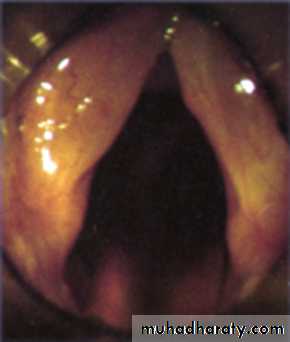

The vocal cords are two fold-like structures extending from the thyroid cartilage to the vocal process of the arytenoid cartilage.

The covering epithelium of vocal cords is closely bound to the underlying structure and the blood supply is poor, hence the pearly white appearance.

The epithelium lining the larynx is ciliated columnar type except over the vocal cord where it is stratified squamous type.